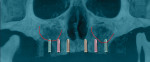

Variations of incorporating zygomatic implants into the severely resorbed maxilla may be part of a conventional type of All-on-4 treatment procedure when sufficient bone exists in the paranasal region for the placement of anterior implant fixtures (Figure 7 through Figure 10). When the paranasal region will not accommodate implant placement, this approach can be expanded to the quad zygoma procedure where two zygomatic implants are inserted in each upper quadrant bilaterally (Figure 11 through Figure 16).18,19

Zygomatic implants are not limited to use in fully edentulous cases. Options exist for partially edentulous patients exhibiting multiple posterior tooth loss with both horizontal and vertical bone loss volume in the ridge crest. The implants may be used in the partially edentulous maxilla when insufficient volume of bone is present as an alternative to osseous grafting of the sinus or crest to enable implant placement in the posterior (Figure 17 through Figure 19). The incorporation of sinus grafting will lengthen treatment time, as the graft will need to mature prior to implant loading if the implant is able to be placed at the time of sinus augmentation. Should the implant not be able to be placed when sinus augmentation is performed, treatment time is further increased and restoration may not be possible for up to 1-year post initial surgery.